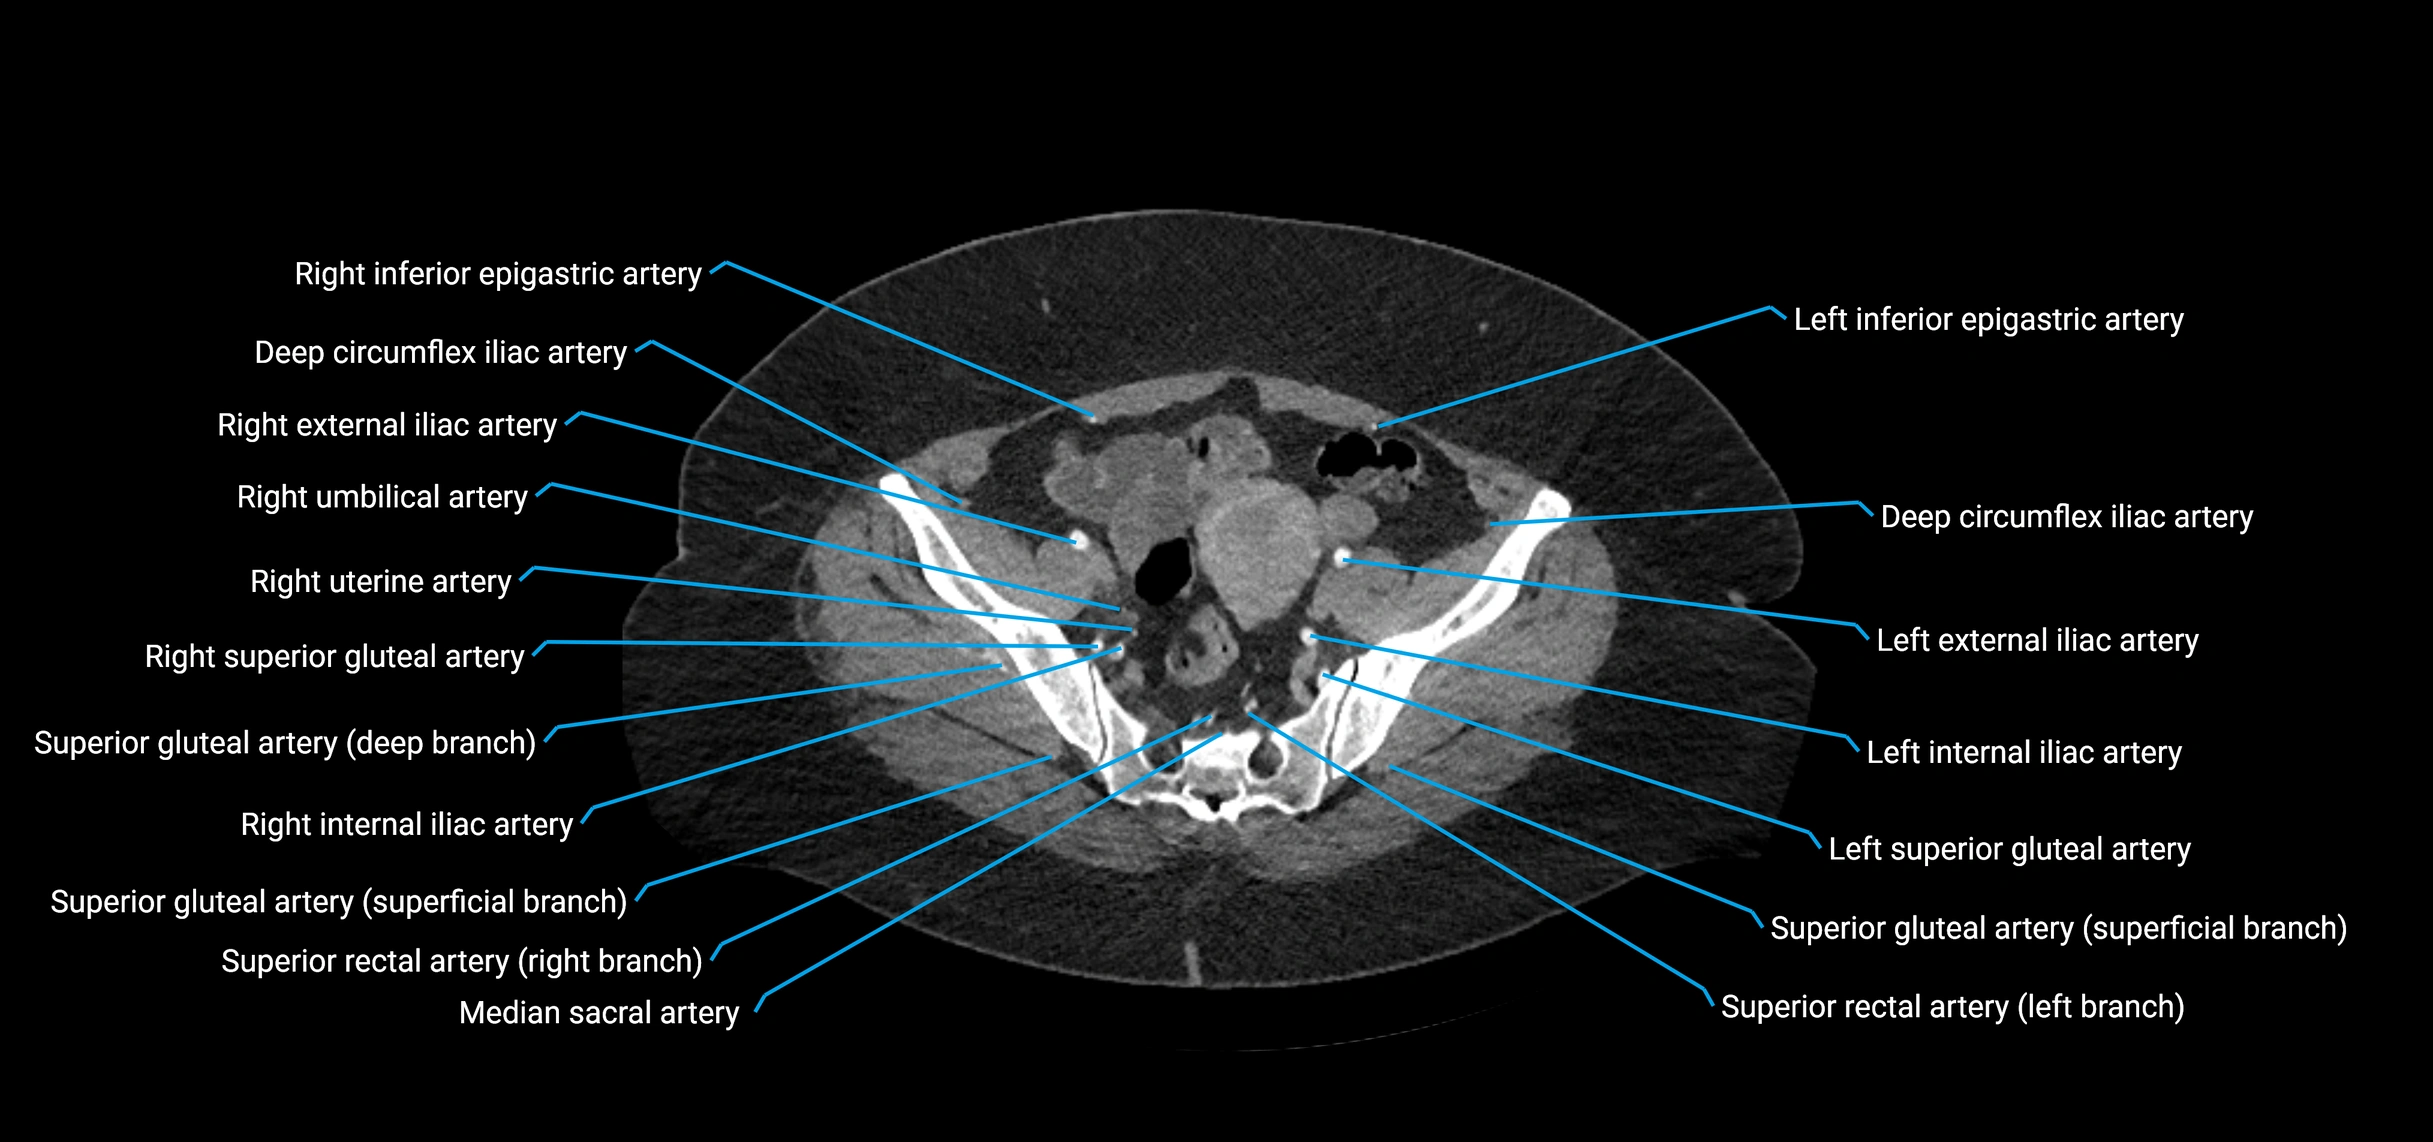

Contrast-enhanced CT (CTA):

• Gold standard for abdominal aortic imaging

• Provides excellent detail of lumen, wall, aneurysm, thrombus, and branch vessels

• Multiplanar and 3D reconstructions help in aneurysm measurement, stent graft planning, and dissection evaluation